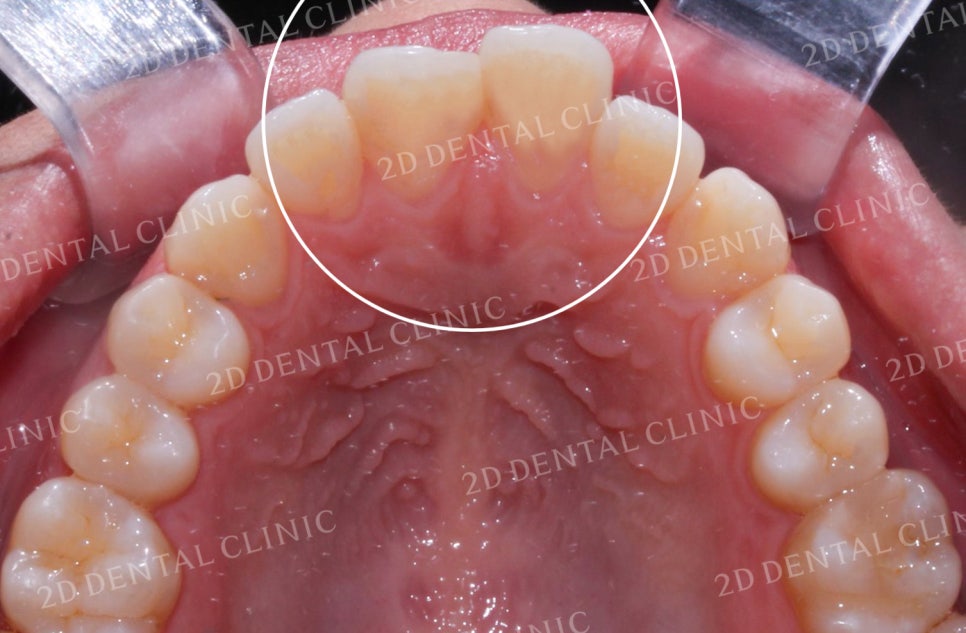

<하악 설측면 사진> <상악 설측면 사진>

상악과 하악의 설측면 사진입니다.

하악의 경우 전치부의 좁은 공간으로 인해

총생이 발견되는데요,

상악 역시 치아가 올바르게 배열되기에

충분한 공간이 확보되지 못한 상태입니다.